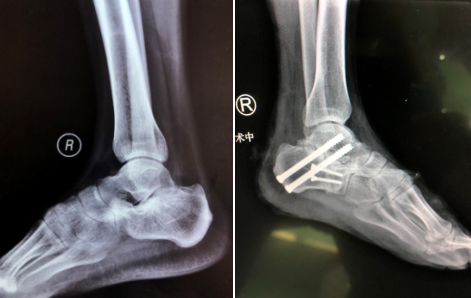

30岁的张师傅是新沂窑湾镇的一个农民。2018年4月,张师傅在家摔伤导致右足跟肿痛一年多,在当地医院检查显示右跟骨骨折,当时未做手术治疗,仅做了保守治疗。一个月前右足跟疼痛加重,X线片显示右跟骨陈旧性骨折,骨折端畸形愈合。张师傅从预告中知道俞教授要来,提出请俞教授做这个手术。俞教授坐诊时,与我院曹广超主任手术团队一起为张师傅做了右跟骨截骨矫形+距下关节融合术。

“手术中,医生把跟骨外侧膨出的骨头削掉,恢复它的长度、宽度与高度,把距下关节给它融合,摆正后足的力线。这样,以后在走路过程中,疼痛会有很大缓解。患者跟骨骨折后没引起重视,保守治疗1年半后,发现一直肿痛,走路疼得厉害没法长时间走,来到咱们医院,检查这是陈旧性骨折,必须通过手术才能解决症状,患者家属也有强烈手术意愿。患者知道俞教授这个月来sararz坐诊,主动预约,顺利做了手术。”手术小组的赵亮医生说。